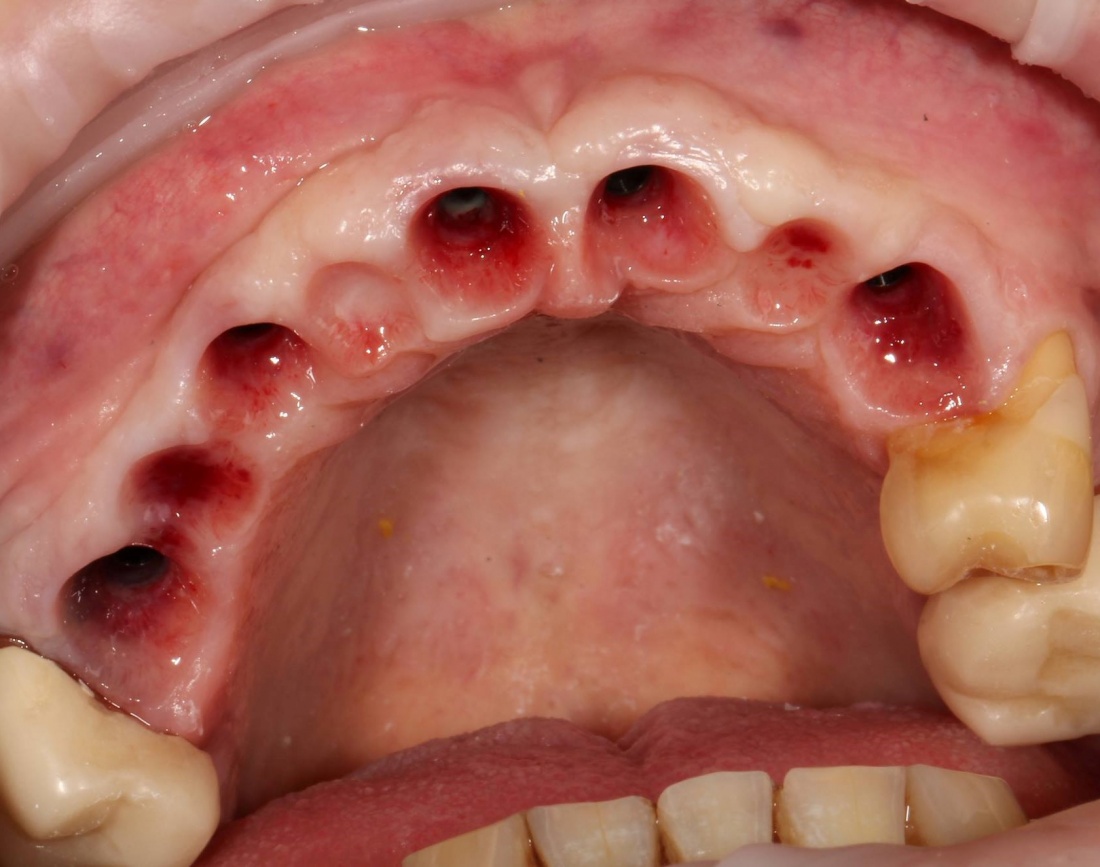

Устанавливаем формирователи десневой манжеты. Сегодня я называю эту процедуру не менее важной, чем любой другой этап имплантологического лечения:

И швы. Просто швы. Никаких дополнительных процедур.

Если честно, то сейчас бы я использовал другой шовный материал и другой тип швов. Одно неизменно, — и я об этом много раз говорил, — самая широкая часть формирователя десны должна находиться на уровне десны. Так, чтобы эффективно отрабатывать т. н. «биологическую ширину».

Через неделю я снял швы, а мой коллега Андрей Карнеев (дело было еще в НИЦ) приступил к изготовлению протезов. На это ушло полторы недели: